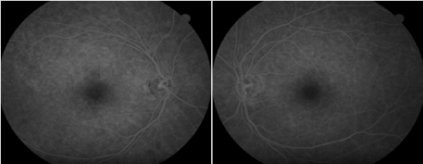

Fluorescein angiography of both eyes was normal (Figure 2). Optical coherence tomography revealed small defect of approximately 60 µm in the outer retinal layers with disruption of ellipsoid and interdigitation zones (Figure 3).

Figure 2. Fluorescein angiography does not reveal a transmission defect or other abnormality.